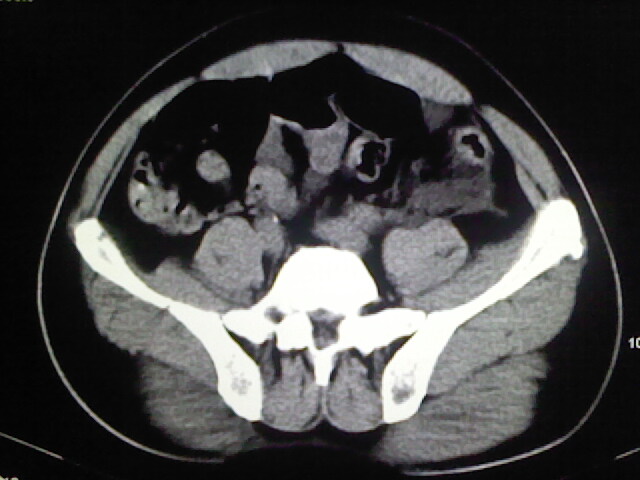

以下是引用zsl6918在2009-2-7 7:29:00的发言:[br]请提供介入的方式方法,肾及输尿管改变考虑与介入损伤有关,漏了,尿液外渗。

以下是引用余辉在2009-2-7 8:27:00的发言:[br]可能是硬化剂烧穿囊壁进入肾盂输尿管了,尿漏。不除外介入或碎石术后合并感染[br]患者术后怀疑结石,接着就碎石了?就怀疑没有确诊吗?碎石用的什么方法?气压弹道还是体外超声?如果这样的话责任人都难找

以下是引用随光逐影在2009-2-7 8:46:00的发言:[br]支持3楼意见。[br]另:不排除左肾及肾周感染可能。